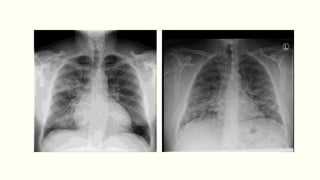

Chest X-ray

Lobar pneumonia

ļ‚§Patchy opacification evolves into homogeneous consolidation

of affected lobe

ļ‚§Air bronchogram (air-filled bronchi appear lucent against

consolidated lung tissue) may be present.

Bronchopneumonia: Typically patchy and segmental shadowing

Complications: Para-pneumonic effusion, intrapulmonary

abscess or empyema

Staph.aureus: Suggested by multilobar shadowing, cavitation,

pneumatocoeles and abscesses